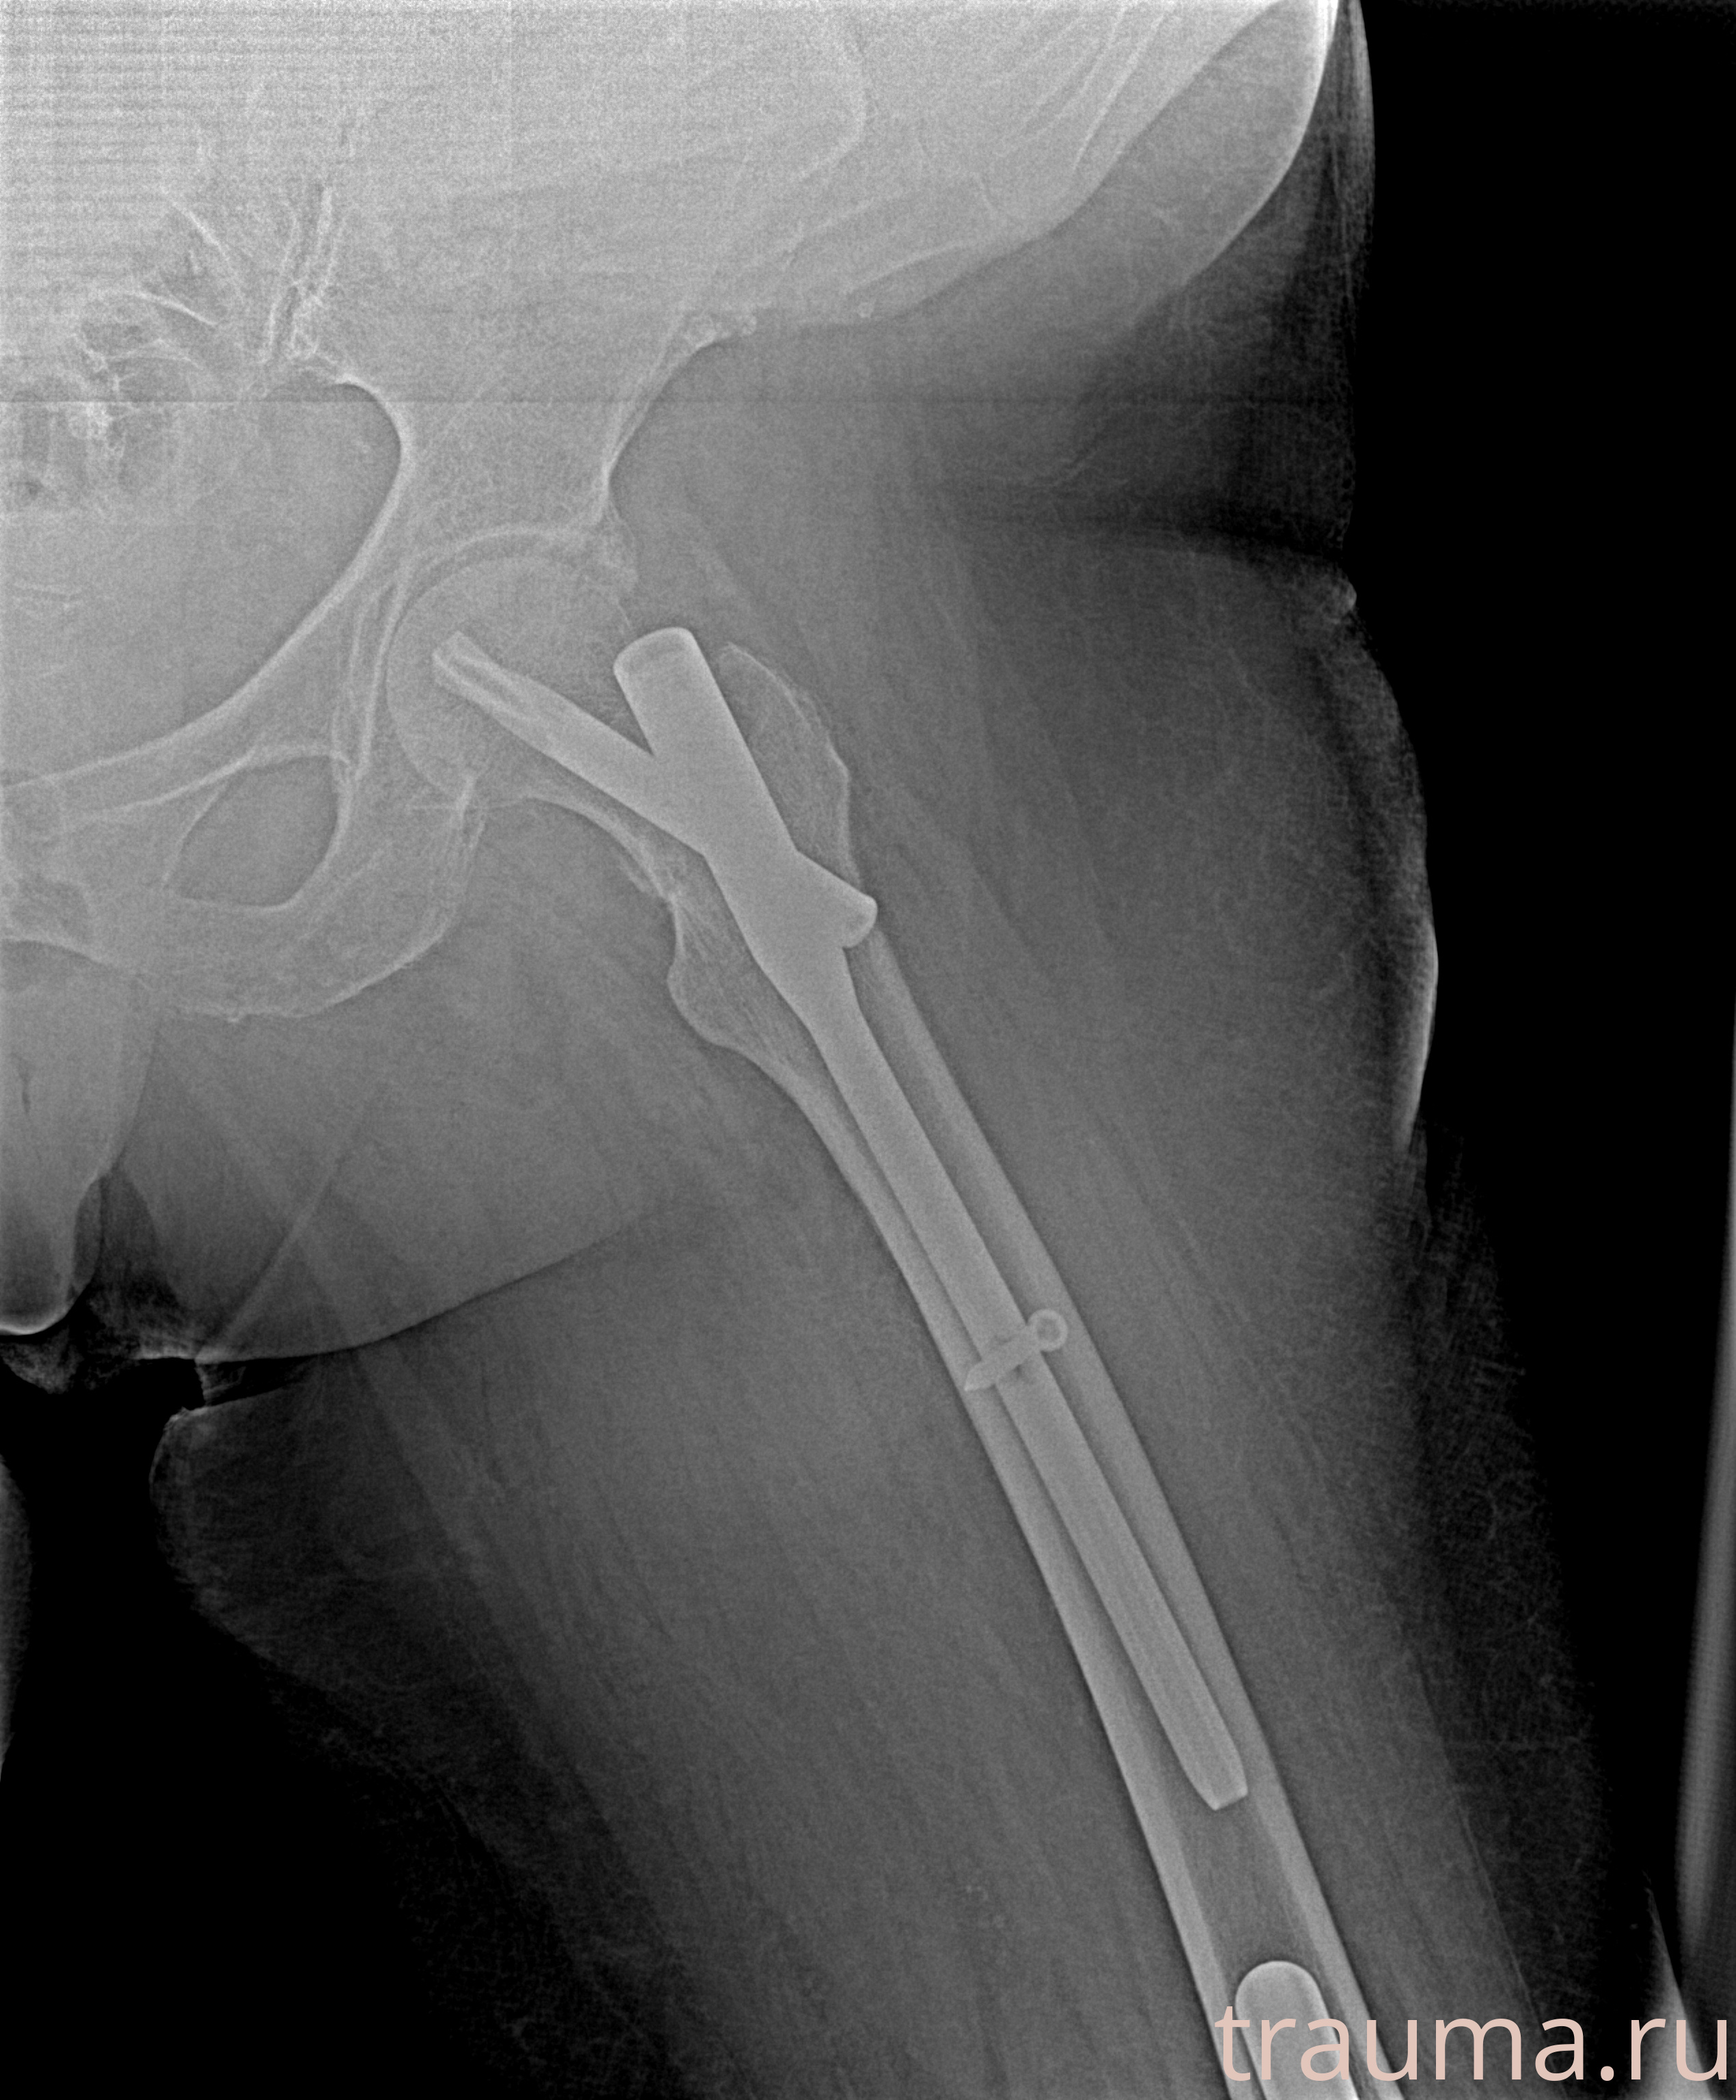

Рентгенограммы